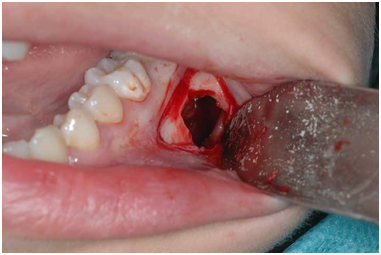

An asymptomatic, 16 years old Caucasian female was referred to a private office for evaluation of an impacted third molar located on the left mandible, with an unremarkable medical history. Intraoral and extra oral examination identified no signs of oral pathology. Panoramic radiograph revealed a unilocular radiolucency with clear margins extending within the molar area of the left mandible (Figure 1). The lesion was scalloping between the aforementioned teeth without any signs of root resorption, affecting the route of inferior alveolar nerve. The differential diagnosis included keratocystic odontogenic tumor, ameloblastoma and traumatic bone cyst. A surgical biopsy was suggested and the patient was operated under local anaesthesia. A mucoperiosteal flap was raised and under saline irrigation a bone window below the roots of 1st and 2nd molars was detached to expose the lesion (Figure 2). The bone cavity was completely empty of tissue or fluid without any epithelial lining while the inferior alveolar nerve was lying within it. The operative findings confirmed the diagnosis of TBC. Post operative course was uneventful with satisfactory bone healing on a follow-up panoramic radiograph.

Figure 1

Figure 2